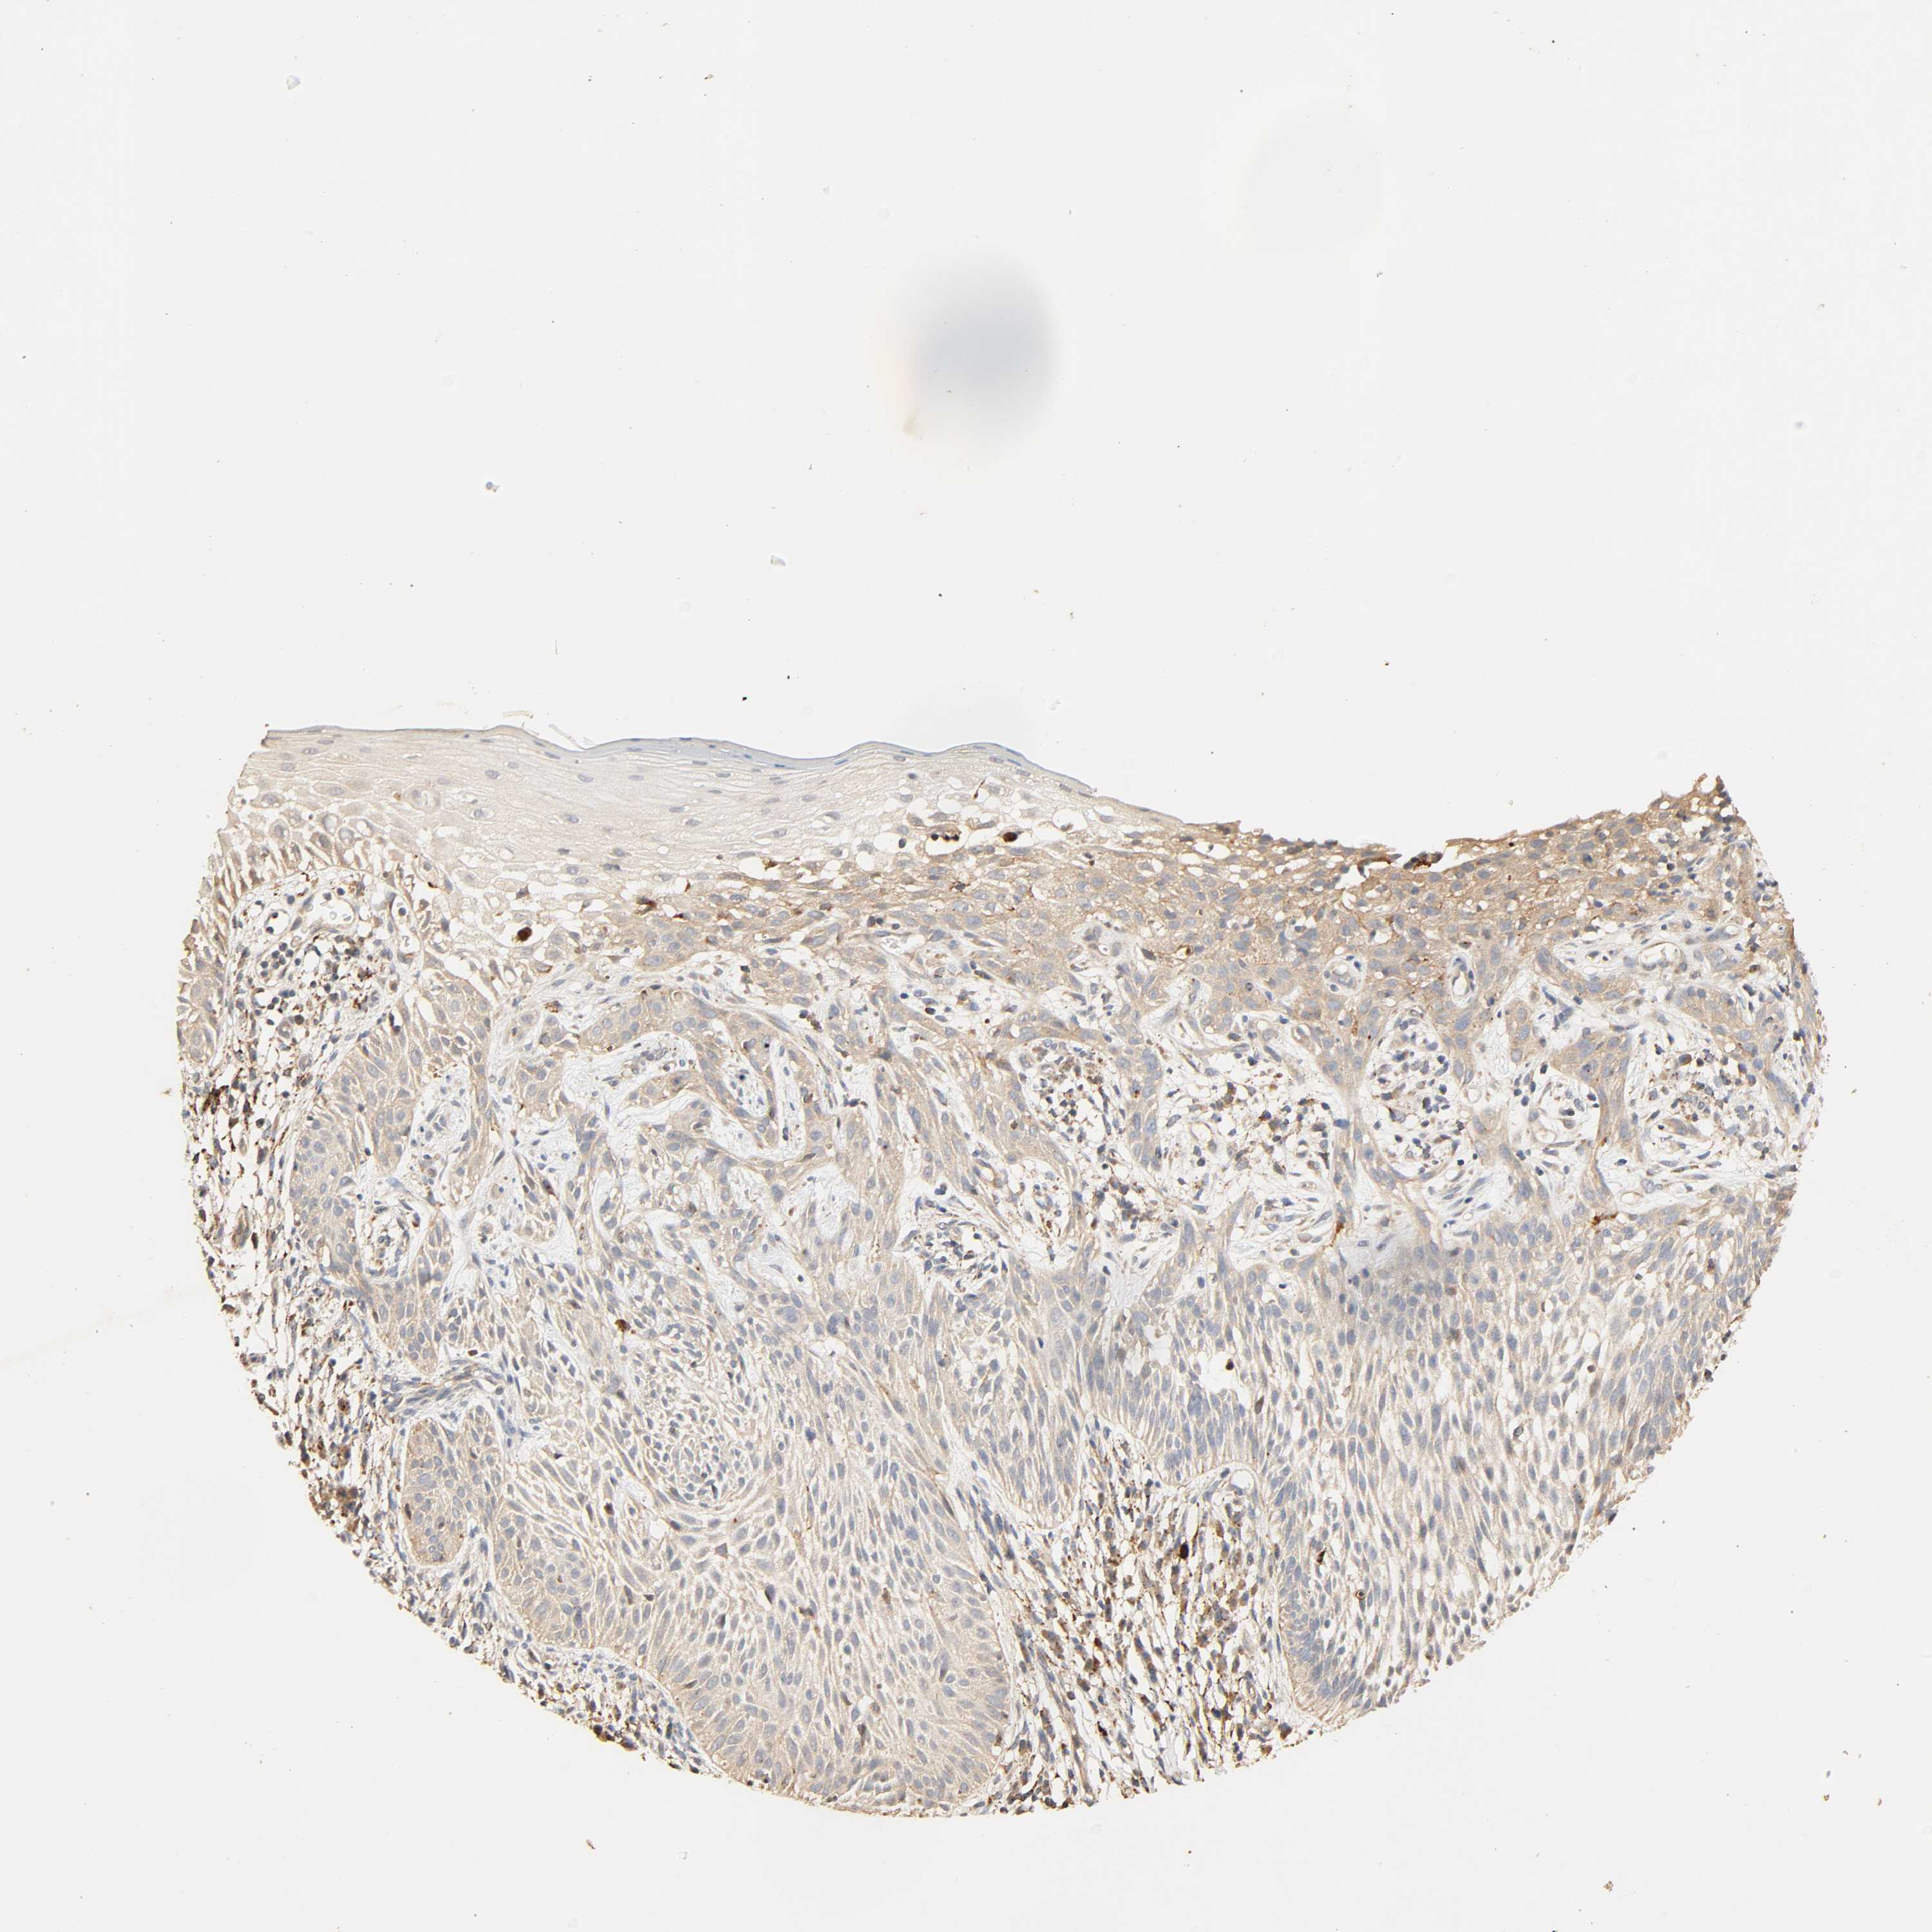

Basal cell and squamous cell cancer

SKIN CANCER - Protein expressioni

A mouse-over function shows sample information and annotation data. Click on an image to view it in a full screen mode. Samples can be filtered based on level of antibody staining by selecting one or several of the following categories: high, medium, low and not detected. The assay and annotation is described here.

Each image is clickable and will lead to virtual microscopy that enables deeper exploration of all samples and also displays staining intensity scores, fraction scores and subcellular localization as well as patient and tissue information for each sample.

Antibody HPA030262

Antibody HPA047825

Antibody CAB005184

Basal cell carcinoma

Squamous cell carcinoma, NOS

Squamous cell carcinoma, metastatic, NOS